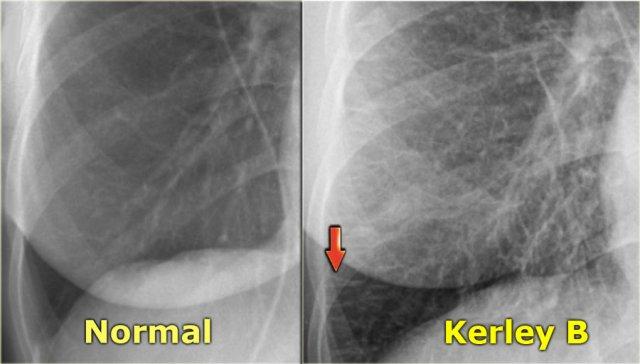

Kiểu hình ảnh dạng lưới trong suy tim sung huyết

Hãy quan sát các hình ảnh rồi tiếp tục đọc.

Các dấu hiệu bao gồm:

- Phim cũ bình thường ở bên trái.

- Kiểu hình ảnh dạng lưới đặc biệt ở vùng đáy phổi. Có thể thấy một số đường Kerley B.

- Tim to.

- Tràn dịch màng phổi bên trái.

- Mạch máu phổi nổi bật hơn so với phim cũ.

Dựa trên các dấu hiệu này, chúng ta có thể kết luận đây là suy tim sung huyết.

Đây là kiểu hình ảnh mô kẽ phổ biến nhất trên phim X-quang ngực thẳng.

Phù mô kẽ thường biểu hiện dưới dạng lưới.

Đôi khi có thể thấy các đường Kerley B.

Đây là một ví dụ khác.

Đường Kerley B là các đường nằm ngang dài 1-2 cm gần màng phổi bên.

Chẩn đoán phân biệt chính của đường Kerley B là:

- Phù mô kẽ trong suy tim

- Viêm bạch mạch do ung thư (lymphangitis carcinomatosa)

Đây là một phim X-quang ngực thẳng khác với phù mô kẽ và đường Kerley B ở bệnh nhân suy tim sung huyết.

CT cho thấy dày vách liên tiểu thùy.